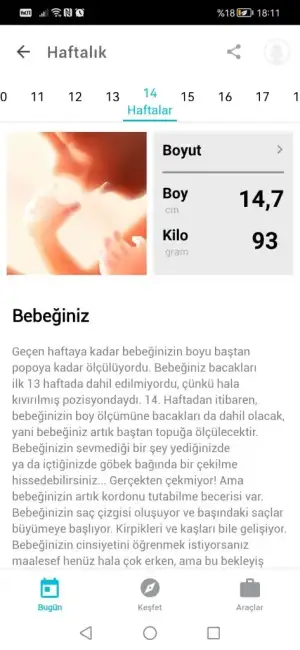

ruzgarimin fotosu kaybettiğim. yavrucum babasına benziyorduMaşallahnasıl tatlıymış ya senin standart yüksek acaba kız bebekler mi böyle güzel görünüyor diye düşündüm